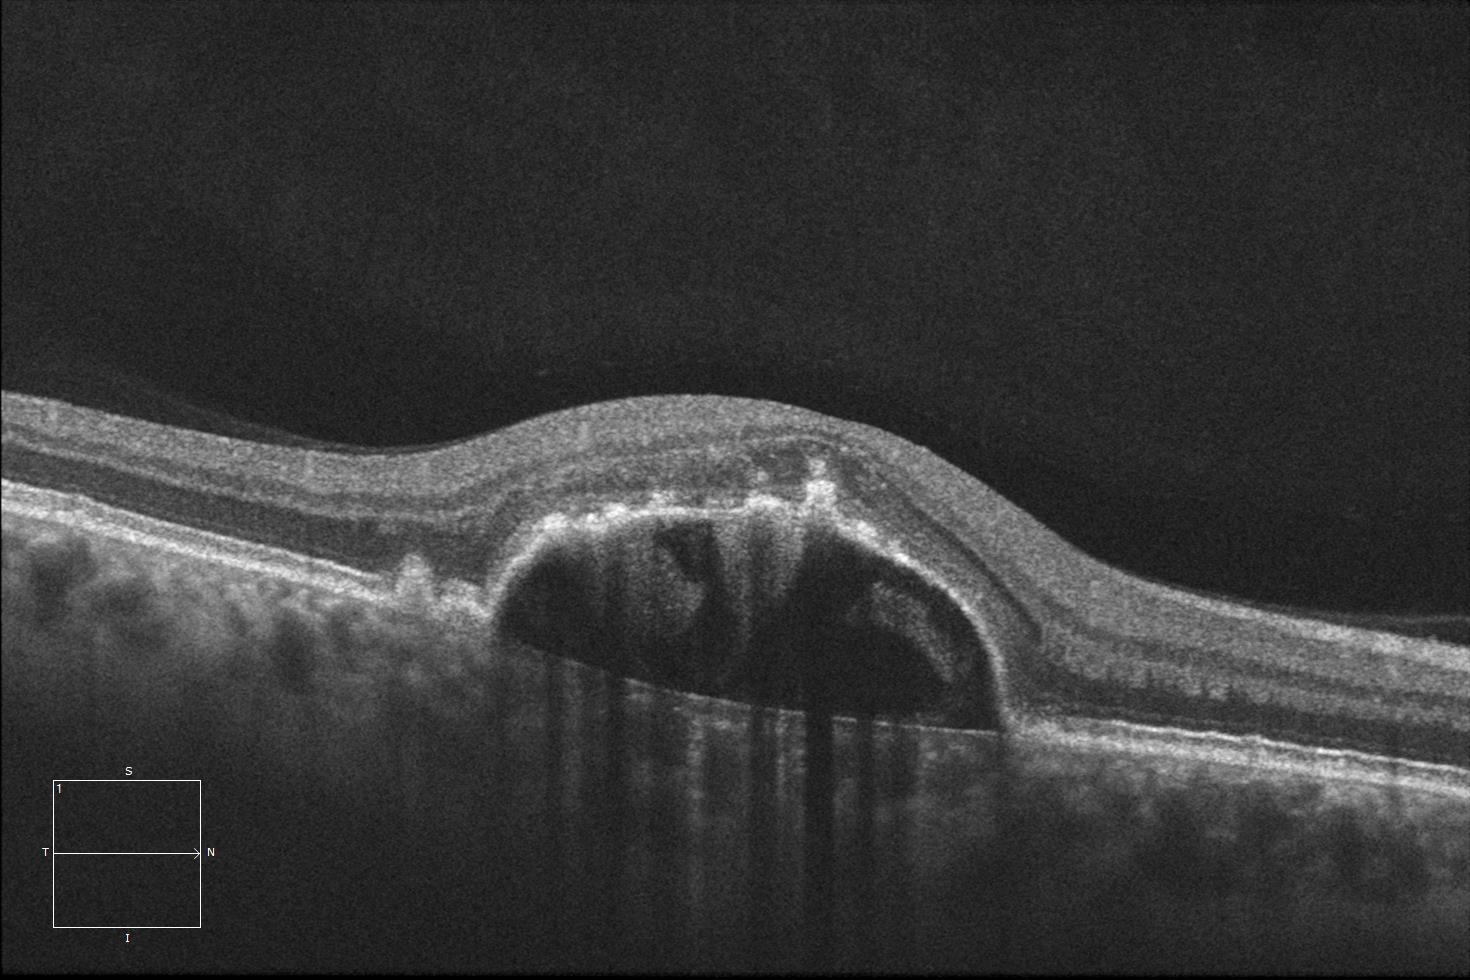

Whilst most retinal diseases are obvious on clinical examination, some diseases can be difficult to detect and in that instance OCT scans

can be useful. OCT scanning is also essential for treating the most common cause of blindness in Australia, wet macular degeneration.